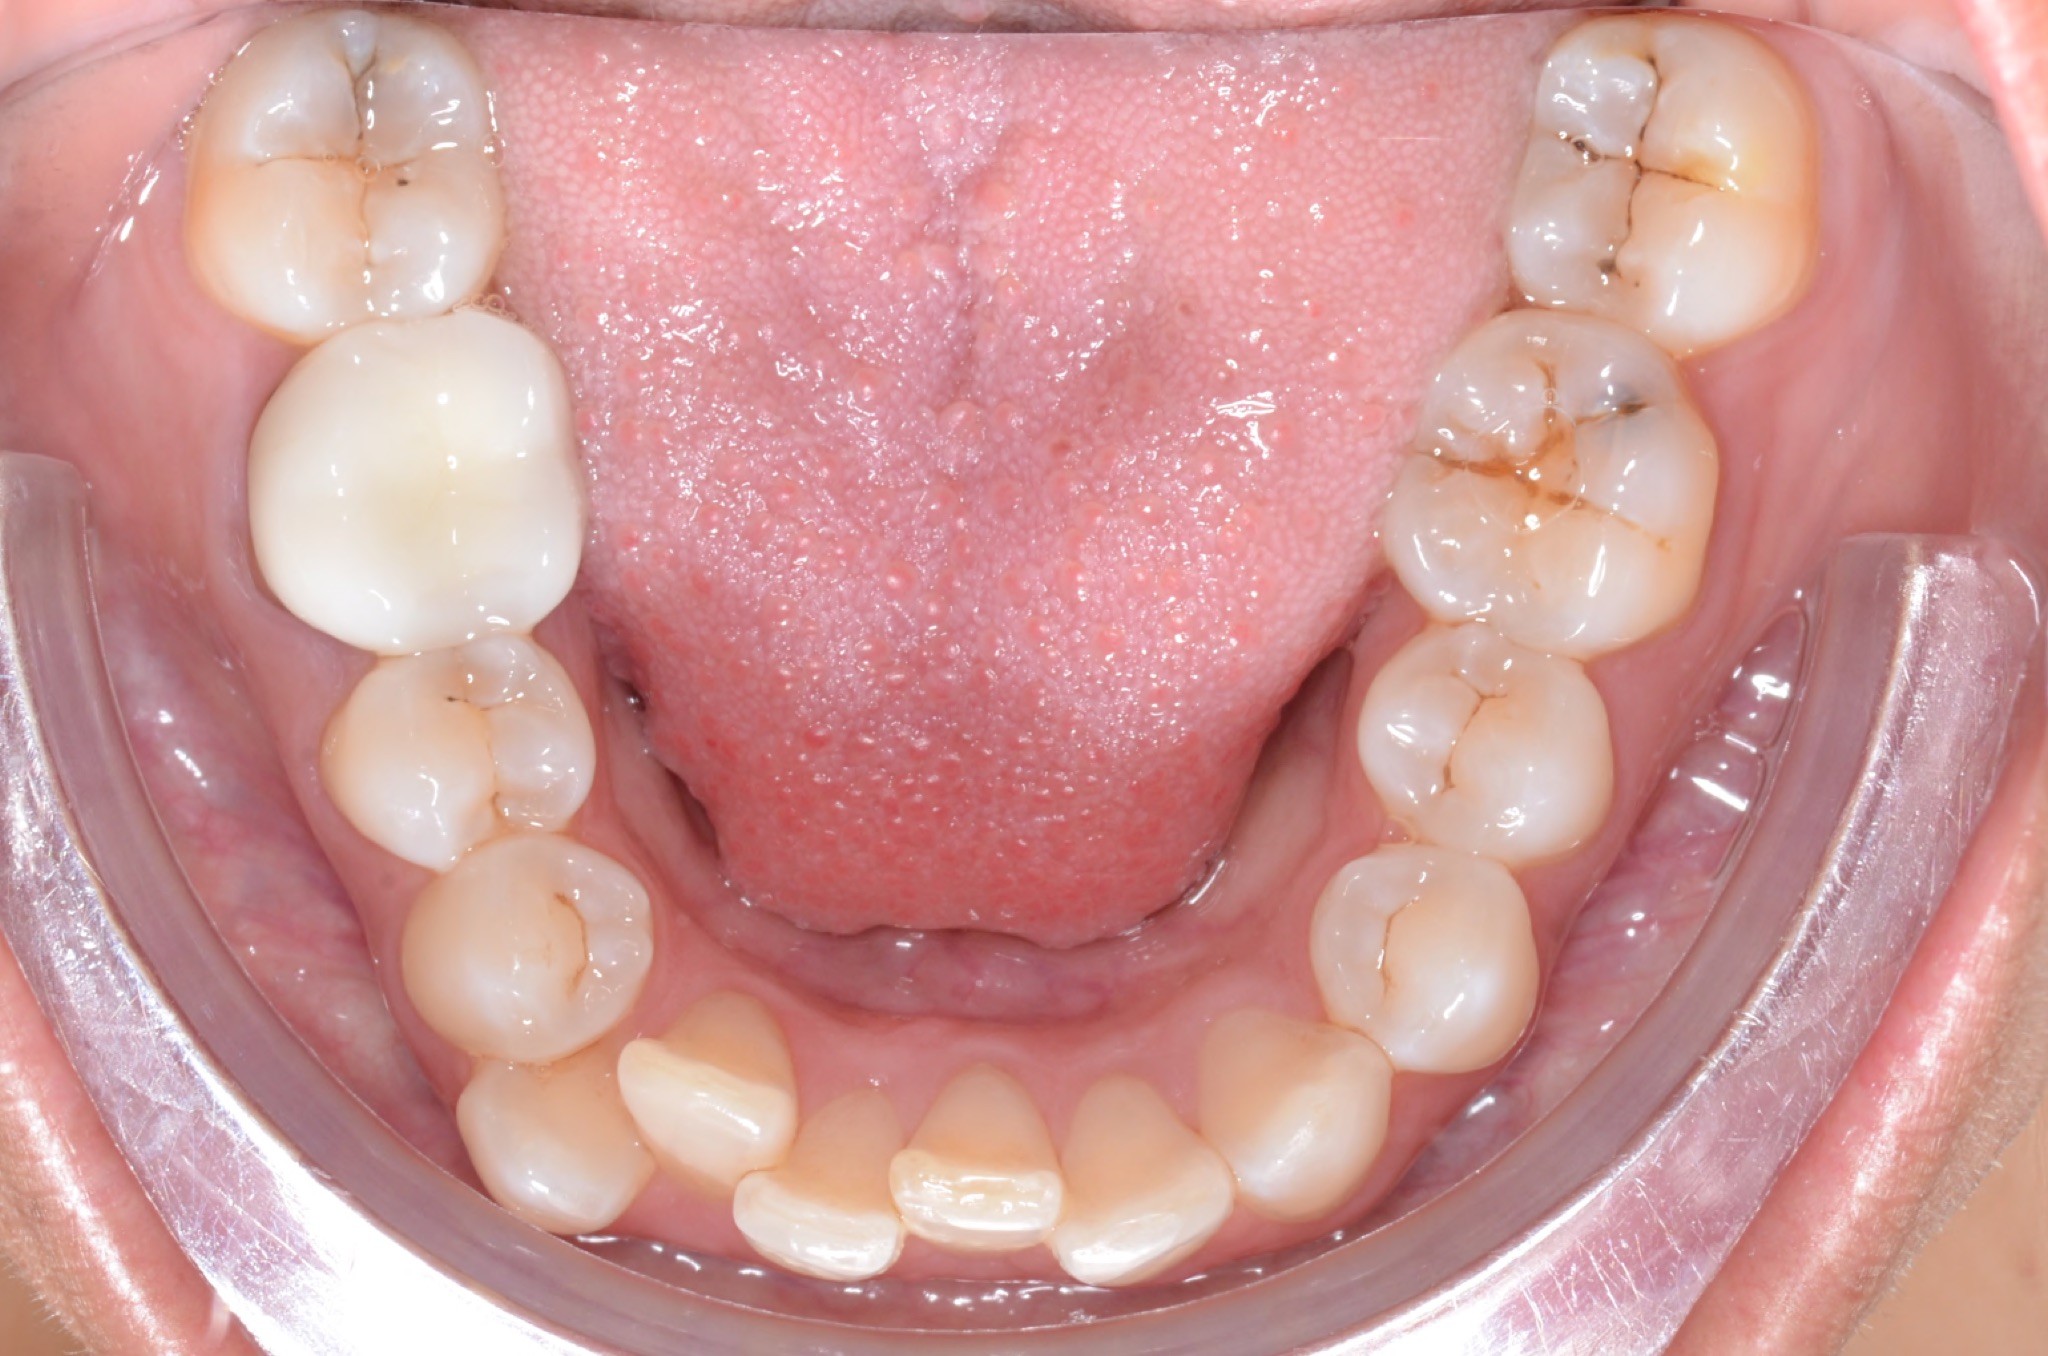

Diagnosis: Lower anterior crowding, LL3 crossbite, deep bite, missing UL6.

Adjuncts: Bite ramps, attachments, IPR

Initial treatment

INTRAORAL